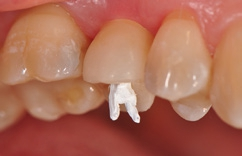

Für den Reentry wurde für das Einbringen des Gingivaformers eine minimale krestale Inzision angelegt (Abb. 13). Nach Abheilung der Weichgewebe (Abb. 14) konnte 2 Wochen später mit Reposition des Abformpfostens geschlossen abgeformt (Abb. 15) und das Meistermodel erstellt werden Da es sich um ein 2-teiliges Implantatsystem handelt und die Abutments ebenfalls aus hochfester ATZ-Keramik bestehen, lassen sich diese – falls nötig – entweder in der Praxis oder im Dentallabor durch Beschleifen individualisieren (Abb. 16). Für NobelPearl stehen sowohl gerade als auch 15° abgewinkelte Abutments mit 1 mm und 3 mm Gingivahöhe zu Verfügung. Im CAD/CAMVerfahren wurde eine monolithische Zirkonkrone aus Zolid FX (Amman Girrbach) mit okklusalem Zugang zum Schraubenkanal gefertigt (Dentallabor Studio für Zahntechnik, Dirk Tartsch).

Verklebung der Krone

Nach der Einprobe von Abutment und Krone (Abb. 18 und 19) erfolgt ihre Verklebung analog einer Titanklebebasis entweder extraoral im Dentallabor oder, wie in diesem Fall, intraoral. Der Vorteil des Verklebens im Patientenmund liegt darin, dass eventuell auftretende Spannungen zwischen Abutment und Implantat abgefangen werden können. Solche Spannungen können bereits durch nicht ganz korrekte Reposition des Abformpfostens bei einer geschlossenen Abdrucknahme ausgelöst werden, durch kleine Ungenauigkeiten bei der Gestaltung der Kontaktpunkte oder aber auch durch das – wie bei jedem Implantatsystem mehr oder weniger vorhandene – „Spiel“ zwischen Implantat, Abformpfosten, Laborimplantat und Abutment. Dabei kann Titan als elastisches Metall solche „Mikrospannungen“ eher ausgleichen als die harte, nicht elastische Keramik.